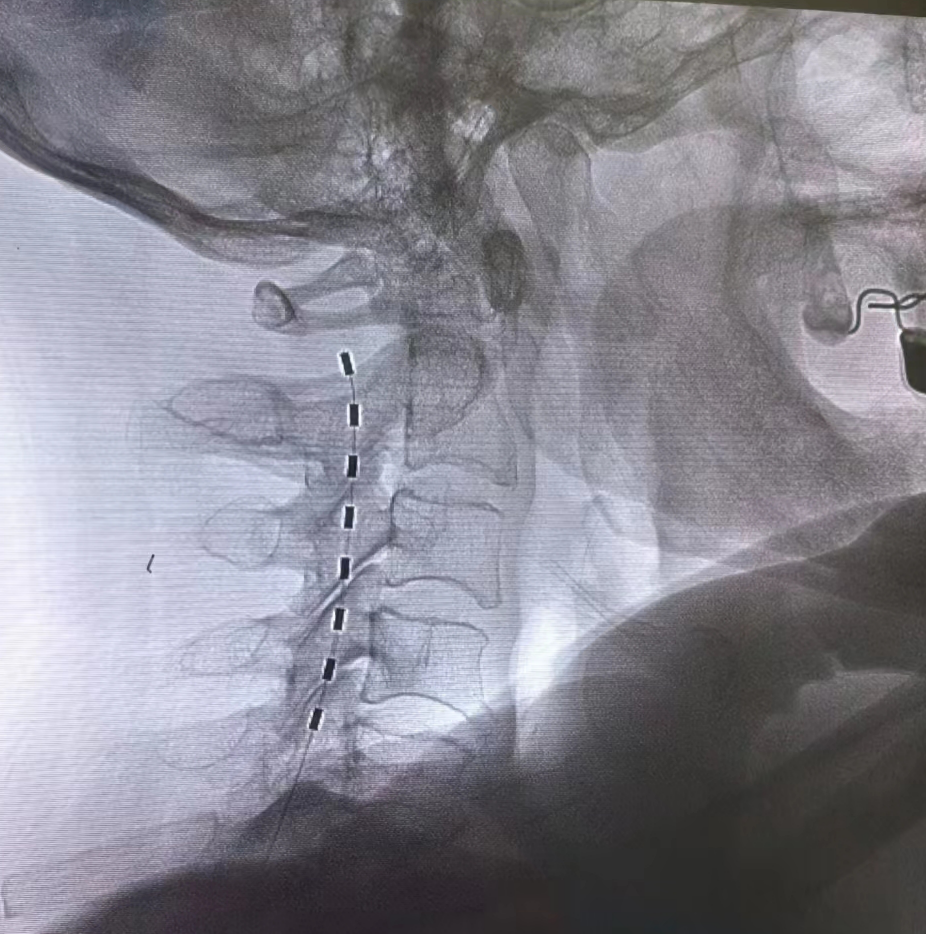

神经调控:包括神经射频、电刺激等,是目前治疗带状疱疹后神经痛最有利的手段。通过干预神经电信号,减少疼痛传递,促进镇痛物质释放,可以达到更佳持久的镇痛效果。尤其适用于后遗神经痛的治疗。